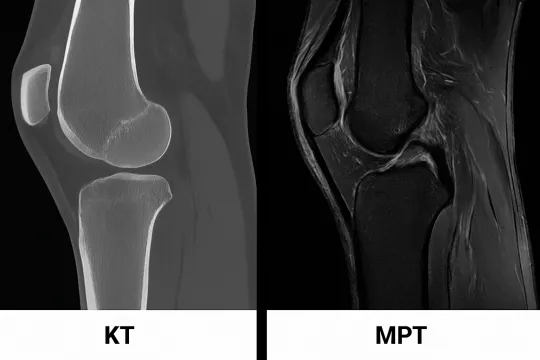

Что лучше сделать для коленного сустава: КТ или МРТ?

Выбор между КТ и МРТ коленного сустава необходимо осуществлять в зависимости от клинической ситуации и предполагаемых диагнозов. КТ зачастую применяется для выявления повреждений костей, таких как переломы или остеоартрит. Этот метод отображает структуру костей и может дать обширные данные о состоянии суставного пространства. КТ также полезна для быстрой диагностики в экстренных ситуациях.

С другой стороны, МРТ более эффективно показывает мягкотканевые структуры, такие как связки, мениски и суставная капсула. Если вероятность наличия повреждений мягких тканей высока, тогда именно МРТ будет более подходящим выбором. Кроме того, данный метод не использует ионизирующее излучение, что делает его более безопасным в долгосрочной перспективе.